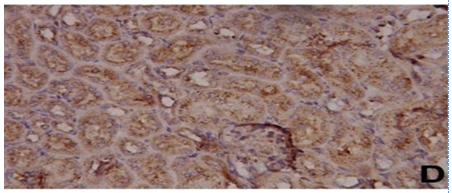

Fig. 6: Photomicrographs of kidney tissue. Where A) represents control, B) aluminum chloride AlCl3), C) zinc oxide nanoparticles (ZnO NPs) and D) aluminum chloride (AlCl3)+zinc oxide nanoparticles (ZnO NPs)

Effect of ZnO NPs and/or AlCl3 treatment on kidney histopathology

As shown in fig. 6, the renal tissue of the control and ZnO NPs-treated animals showed an identical kidney structure with normal renal tubules and glomeruli. AlCl3 intoxication for 42 d resulted in swelling of epithelial cells, edema of the inter-tubular spaces, focal hemorrhage, inflammatory cell infiltration, vacuolation, and development of intraluminal casts as observed previously [5]. Pre-administration of ZnO NPs minimized the pathological alterations induced by AlCl3 exposure in kidney tissue.